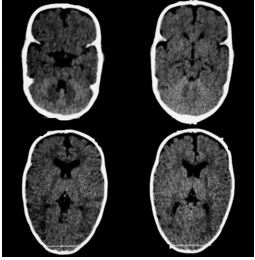

Mas doutor, quando é preciso de tomografia do crânio? Quase nunca, é solicitado quando existe alguma dúvida e mais ainda nas craniossinostoses sindrômicas.

> Escafocefalia, é a sinostoses mais comum, vista mais no sexo masculino,o que acontece é o fechamento da sutura sagital levando o crânio ao formato de barco. A cirurgia é indicada de preferencia antes do sexto mês de vida, mas se a criança tiver mais idade, não impede de ser operado.

> Trigonocefalia, é o fechamento precoce da sutura metópica, o formato do crânio é em forma de pera o qual realiza compressão do lobo frontal que pode levar aumento da pressão intracraniana em até 20% dos casos. Crianças com mais de 5 anos que não foram operados, tem literatura que fala em dificuldade do aprendizado.

> Plagiocefalia, é o fechamento precoce da sutura coronal unilateral (plagiocefalia anterior) ou da sutura lambdoide (plagiocefalia posterior), afeta mais o sexo feminino e o lado direito é mais afetado. A criança tem um rostro em “arlequim” já que uma das órbitas esta retraída para cima e para tras.

> Braquicefalia, é o fechamento prematura de ambas suturas coronais ou lambdoides.